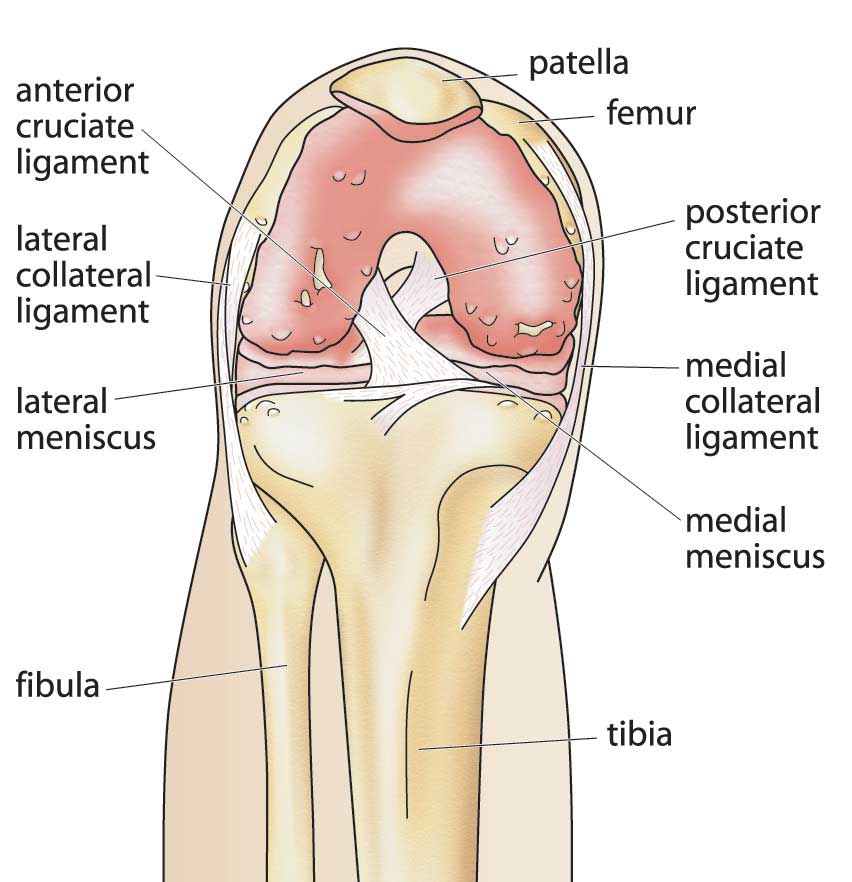

Knee Bones Anatomy Function Injuries Knee Pain Explained shop, Patellar Fractures Broken Kneecap OrthoInfo AAOS shop, Patella Kneecap Anatomy and Function shop, Knee Anatomy Arthritis health shop, The Kneecap Patella and Knee Joint Saint Luke s Health System shop, Patella Wikipedia shop, Knee Joint Function Anatomy shop, Patella the Knee Cap shop, Normal Anatomy of the Knee Joint Middletown Knee Treatment Old shop, Where or Where Has My Patella Gone Direct Orthopedic Care shop, Knee Joint Anatomy and Arthritis SHELBOURNE KNEE CENTER shop, Physiotherapy in Calgary for Knee Pain Bipartite Patella shop, Patella Anatomy function and clinical aspects Kenhub shop, Patellofemoral Pain Syndrome My Family Physio shop, Why You Have a Kneecap and How it Unleashes Your Quads shop, Physiotherapy in Calgary for Knee Pain Bipartite Patella shop, Knee Anatomy Sweep shop, Patella Kneecap Bone Xray Front Anterior Stock Illustration shop, Patella Wikipedia shop, Patella Knee cap Joint surgeon shop, Patella Fracture Broken Knee Cap Orthoriverside shop, Patellofemoral Pain Syndrome OrthoInfo AAOS shop, Knee replacement Understanding your knee shop, Is there something wrong with my kneecap Coastal Orthopedics shop, Has Anyone Dealt With a Knee Cap Bone Spur Training TrainerRoad shop, What You Need to Know About Kneecap Injuries Sports health shop, Knee Trauma Fractures of the Patella Tibial Plateau and Distal shop, Patella or kneecap bone Anatomy bones Leg muscles anatomy shop, Dislocated Kneecap Dislocated Patella for Parents Nemours shop, Kneecap Pain shop, Knee Pain Location Chart SPORT Orthopedics Dallas and Frisco shop, Knee Pain Causes Treatment shop, Why Kneecapping Your Opponent Works shop, Chondromalacia Harvard Health shop, Knee replacement Understanding your knee shop.

Knee Bones Anatomy Function Injuries Knee Pain Explained shop, Patellar Fractures Broken Kneecap OrthoInfo AAOS shop, Patella Kneecap Anatomy and Function shop, Knee Anatomy Arthritis health shop, The Kneecap Patella and Knee Joint Saint Luke s Health System shop, Patella Wikipedia shop, Knee Joint Function Anatomy shop, Patella the Knee Cap shop, Normal Anatomy of the Knee Joint Middletown Knee Treatment Old shop, Where or Where Has My Patella Gone Direct Orthopedic Care shop, Knee Joint Anatomy and Arthritis SHELBOURNE KNEE CENTER shop, Physiotherapy in Calgary for Knee Pain Bipartite Patella shop, Patella Anatomy function and clinical aspects Kenhub shop, Patellofemoral Pain Syndrome My Family Physio shop, Why You Have a Kneecap and How it Unleashes Your Quads shop, Physiotherapy in Calgary for Knee Pain Bipartite Patella shop, Knee Anatomy Sweep shop, Patella Kneecap Bone Xray Front Anterior Stock Illustration shop, Patella Wikipedia shop, Patella Knee cap Joint surgeon shop, Patella Fracture Broken Knee Cap Orthoriverside shop, Patellofemoral Pain Syndrome OrthoInfo AAOS shop, Knee replacement Understanding your knee shop, Is there something wrong with my kneecap Coastal Orthopedics shop, Has Anyone Dealt With a Knee Cap Bone Spur Training TrainerRoad shop, What You Need to Know About Kneecap Injuries Sports health shop, Knee Trauma Fractures of the Patella Tibial Plateau and Distal shop, Patella or kneecap bone Anatomy bones Leg muscles anatomy shop, Dislocated Kneecap Dislocated Patella for Parents Nemours shop, Kneecap Pain shop, Knee Pain Location Chart SPORT Orthopedics Dallas and Frisco shop, Knee Pain Causes Treatment shop, Why Kneecapping Your Opponent Works shop, Chondromalacia Harvard Health shop, Knee replacement Understanding your knee shop.